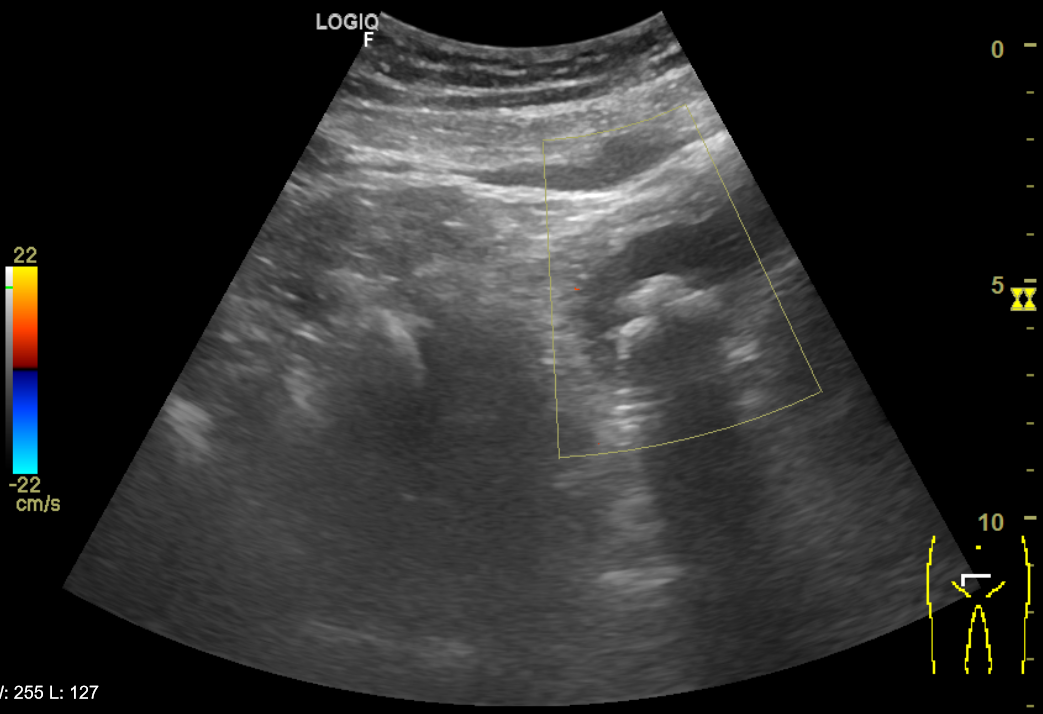

Riñones de morfología y tamaño normales. No se aprecian colecciones intrarrenales ni perirrenales. Sin ectasia de sistemas excretores. Quiste cortical simple en polo superior de riñón izquierdo de 6x6cm. Vejiga poco replecionada de paredes uniformemente engrosadas y trabeculadas. Múltiples imágenes hiperecogénicas con ausencia de registro Doppler y con sombra posterior que sugiere cistolitiasis. Próstata de aspecto normal con volumen de 21 cc. Volumen premiccional de 89 cc y posmiccional de 11 cc.

Juicio clínico: Litiasis en la vejiga. Diagnóstico diferencial: Tumor de vejiga/Hipertrofia benigna de próstata/Infección del trato urinario.